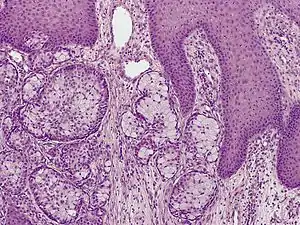

| Eccrine carcinoma, alveolar type | |

Eccrine carcinoma is a rare skin condition characterized by a plaque or nodule on the scalp, trunk, or extremities.[1]: 669 It originates from the eccrine sweat glands of the skin, accounting for less than 0.01% of diagnosed cutaneous malignancies.[2] Eccrine carcinoma tumors are locally aggressive with a high rate of recurrence. Lack of reliable immunohistochemical markers and similarity to other common tumors has made identification of eccrine carcinoma difficult.[2]